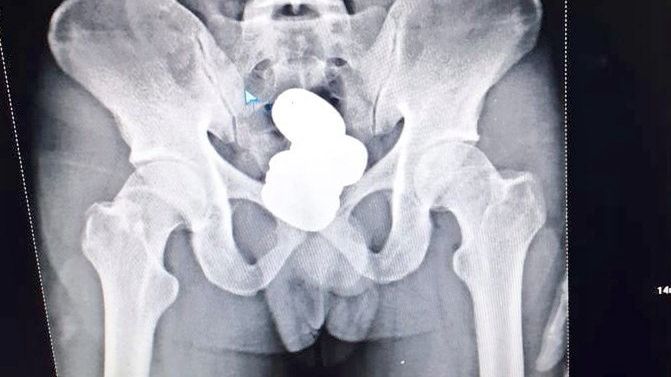

Po wstępnym przesłuchaniu mieszkaniec Kozkihode w stanie Kerala został zabrany do gabinetu lekarskiego, gdzie wykonano mu prześwietlenie rentgenowskie jamy brzusznej. Badanie wykazało, że głęboko w odbycie Shereefa znajdowały się cztery okrągłe opakowania, zawierające złoto w formie pasty.

Paczuszki zostały odzyskane w szpitalu. Ich waga wyniosła 909,7 g. Centralne Siły Bezpieczeństwa narodowego podały, że złoto wyciągnięte z odbytu mężczyzny jest warte około 4,2 miliona rupii, co w przeliczeniu daje ponad 224 tysiące złotych. Mohammed Shereef został następnie przekazany do departamentu celnego lotniska w celu dalszych przesłuchań. Został zatrzymany na 24 godziny, a następnego dnia wyszedł za kaucją.